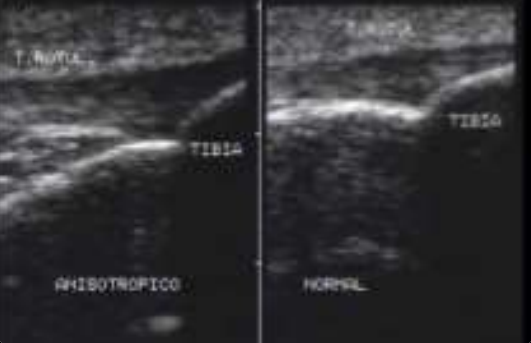

<p>Artefacto</p>

Artefacto

Anisotropia